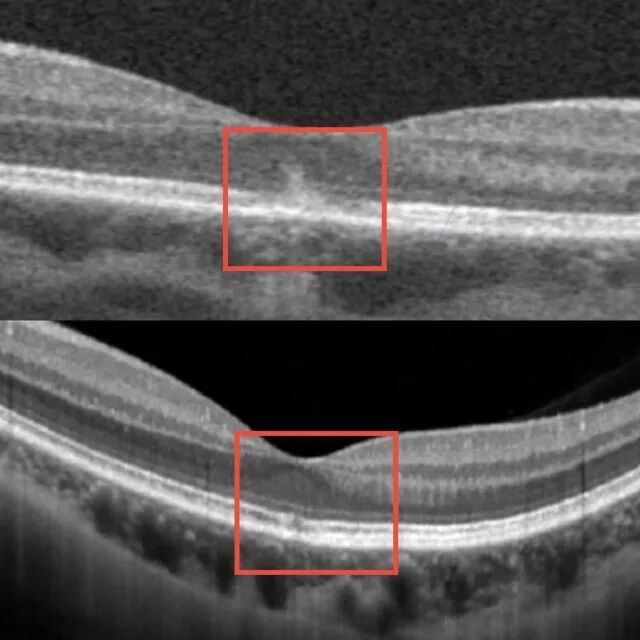

“生理状态下,墨镜或眼罩遮盖眼睛后,瞳孔会自动散大。一旦有强光射入,瞳孔就像一扇敞开的大门,来不及关上,造成人眼视网膜的黄斑部光损伤。”孙传宾说,经检查,患者的视网膜黄斑区出现暗红色斑点,被确诊为“黄斑热损伤”。

“黄斑是眼底最敏锐的感光组织,一旦受损,可能引发不可逆的视功能损害,甚至失明。”他解释,“幸运的是,患者的强光照射短暂,损伤较轻,经过积极的药物治疗,1周后视力明显改善,1个月后恢复正常。若光照强度更强或曝光时间更久,有可能造成不可逆的损伤,甚至致盲。”

黄斑部光损伤修复前后对比图